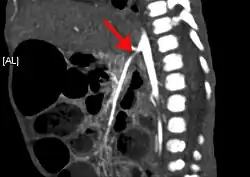

CT angiogram demonstrating stenosis of the superior mesenteric artery.

A computed tomography angiogram showing stenosis of the superior mesenteric artery (arrow).

Abdominal angina is diagnosed by identifying stenosis with imaging.[10] Since the symptoms of abdominal angina overlap with various other disorders, other causes of symptoms are ruled out as a part of the diagnostic process. Gastric ulcers, abdominal aortic aneurysms, and gastrointestinal cancers can have similar symptoms and can be ruled out by esophagogastroduodenoscopy, CT scans, or MR angiogram. Other differential diagnoses include GERD, dietary or food sensitivities, constipation, pancreatitis, abdominal abscess, appendicitis, irritable bowel syndrome, gastroenteritis, hepatitis, and inflammation of the gastrointestinal system.[11] Duplex ultrasound, MR angiography, angiography, and computed tomography angiography can be used to help confirm the diagnosis of abdominal angina.[3] Duplex ultrasound may be used to screen for abdominal angina but is not ideal for visualizing stenosis. Angiography, MR angiography, or CT angiography can be used to further visualize the celiac and mesenteric arteries.[12]